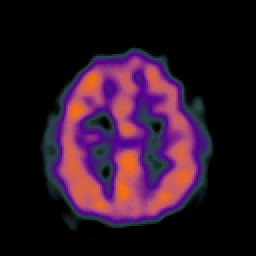

Vascular Malformation (under stress): perfusion SPECT study #2 -- Slice #18

[Home][Help][Clinical] Slice 18